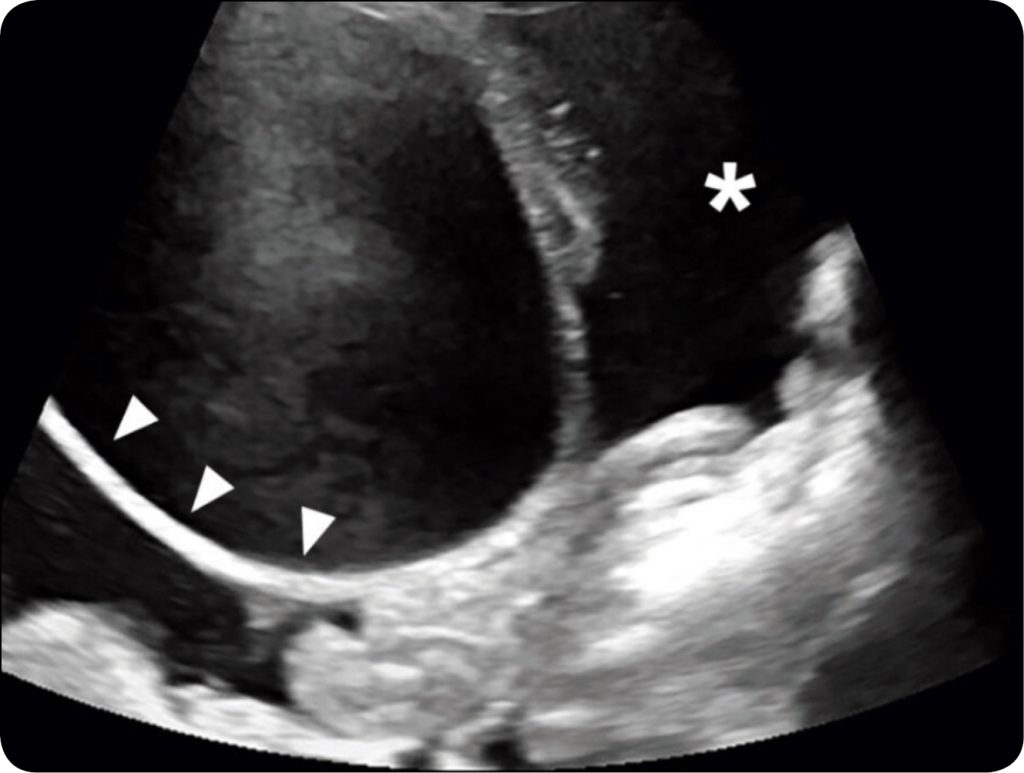

Podejrzenie uszkodzenia układu moczowego nasuwają: dane z wywiadu, prezentowane objawy, wyniki badania klinicznego oraz diagnostyka laboratoryjna. Uzupełnieniem podstawowego badania klinicznego jest diagnostyka obrazowa, ze szczególnym uwzględnieniem badania ultrasonograficznego jamy brzusznej. Pierwszą charakterystyczną cechą obrazu, prowadzącą do wstępnego rozpoznania, jest zobrazowanie hipoechogennego, wolnego płynu w obrębie jamy brzusznej, zgromadzonego w różnej ilości (ryc. 1). Pęcherz moczowy w obrazie USG jest zwykle niewielkich rozmiarów i nie wypełnia się moczem. W niektórych przypadkach możliwe jest zobrazowanie uszkodzenia, co daje możliwość oszacowania spodziewanych trudności zabiegu operacyjnego oraz rokowań dla leczenia zachowawczego w przypadku braku możliwości leczenia operacyjnego. W przypadku przerwania ciągłości moczownika możliwe jest precyzyjne zobrazowanie lokalizacji defektu. W tym przypadku widoczny będzie także płyn w tkance podskórnej w miejscu palpacyjnie dostępnego obrzęku skóry i podskórza. Kolejnym krokiem jest abdominocenteza w celu pobrania płynu otrzewnego. Pobrany płyn wstępnie można ocenić organoleptycznie – płyn będzie mieć zabarwienie i woń moczu. W przypadku wątpliwości możliwym do wykonania testem jest oznaczenie poziomu kreatyniny w pobranym płynie. Wynik przynajmniej dwukrotnie wyższy w stosunku do stężenia kreatyniny w surowicy krwi będzie ostatecznym potwierdzeniem diagnozy uroperitoneum. Wysokie stężenie kreatyniny w jamie brzusznej jest wynikiem nieefektywnej resorpcji przez błony jamy otrzewnej (4, 7). Dzięki temu badanie to jest wartościowym narzędziem diagnostycznym.